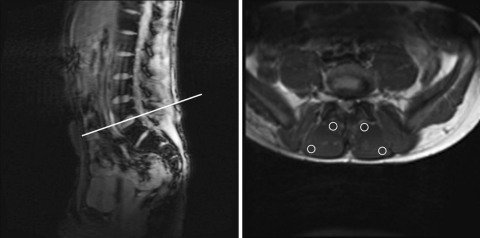

A transaxial slice of 5 mm thickness was obtained from the L4 segmental level and was positioned parallel to the lower end plate of L4 (Fig. 2). A CPMG (Carr Purcell Meiboom Gill) sequence was applied, which was valuable for measuring T2 relaxation times. The sequence had the following parameters: repetition time of 2,500 ms, echo train of 16 equidistant echos ranging from 10.1 to 161.6 ms, 256 mm field of view, 128 × 128 matrix, voxel size 2 × 2 × 5 mm, and a total scan time of 5 min and 24 s. Imaging procedures were identical for the resting scan and the scans after exercise.

Fig. 2.

Left positioning of the transversal slice at the L4 vertebral body. Right transversal slice at the L4 level. Samples of the deep and superficial MF at the left and right side of the body

Next, the regions of interest (ROI) were defined on the T2 image; within the MF muscle, a sample of the deep fibers and a sample of the superficial fibers were outlined, avoiding nonmuscular tissue such as fat, fascia and vessels. The sample of the deep MF was taken immediately adjacent to the lamina of the L4 vertebrae and the sample of the superficial MF was taken at the superficial and lateral border of the muscle [13, 24] (Fig. 2).